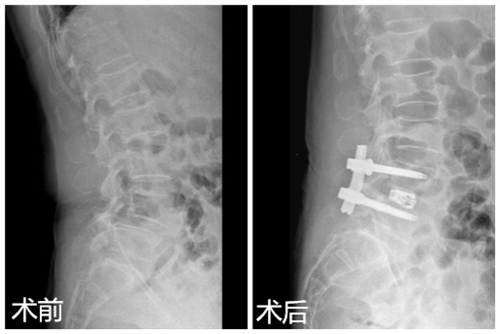

近日,临床医学院/附属医院疼痛科成功为一名腰椎间盘突出症伴腰椎滑脱的患者实施椎间孔镜辅助Endo-LIF腰椎融合术,术后效果良好。该项技术的开展,为腰椎间盘突出症伴腰椎滑脱的患者提供了一个可选择且有效的治疗方法,也标志着临床医学院/附属医院疼痛科的微创治疗水平迈上了一个新台阶。

患者刘女士,60岁,腰部疼痛伴双下肢步行受限半年,近1个月出现间歇性跛行。曾到多家医院求治均效果不佳,后慕名来到临床医学院/附属医院疼痛科求医,门诊医师经过检查后诊断为腰椎间盘突出症伴腰椎Ⅱ度滑脱,椎管狭窄,并建议住院治疗。疼痛科医疗团队为患者进行了仔细的体格检查及影像学评估,做好充分的术前准备后,在DSA引导下成功为患者实施椎间孔镜辅助Endo-LIF腰椎融合术。术后第二天,患者腰部疼痛明显缓解,四天后下地活动,受限恢复正常,患者和家属十分满意。

对于腰椎间盘突出症伴腰椎滑脱,传统的治疗方法是开放手术,由于创伤大,风险高,并发症相对较多,很难为患者和家属接受。融合技术作为脊柱治疗中最重要的技术,逐渐发展为从传统开放走向微创。椎间孔镜辅助Endo-LIF腰椎融合术是将内镜技术、融合技术及经皮内固定技术相结合,该技术是经过腰椎后外侧融合,无需像传统开放手术那样对关节突进行切除,无需干扰腰椎后方的肌肉,对患者腰部解剖结构及稳定性破坏极小,在实现手术切口最小化的同时,达到真正意义上的微创。该技术具有切口小、风险低、创伤小、并发症少的优势,很容易被患者和家属所接受,也是以后脊柱外科发展的方向。